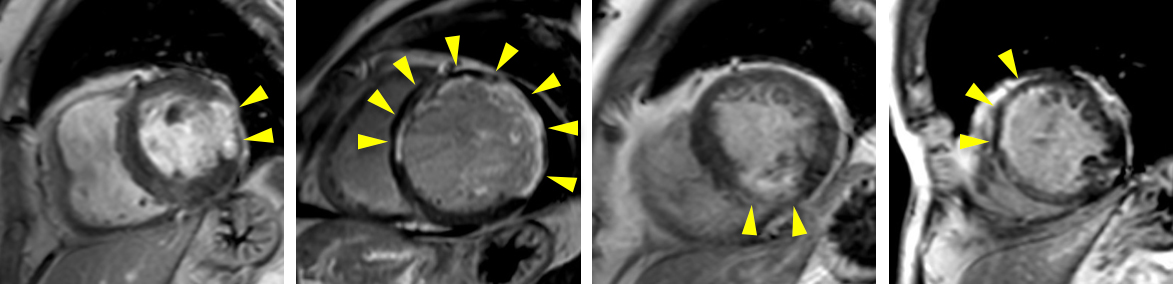

急性心筋梗塞の1例:シネMRI画像(左から中央)では、左心室の一部で収縮が低下している領域があり、心筋の浮腫(T2)画像では、同部位に信号値の高い部分を認め、急性心筋梗塞の所見となります。

心筋遅延造影MRI:造影剤を投与することで,心筋梗塞部位が染まり(矢頭),心筋梗塞の程度を評価することができます.